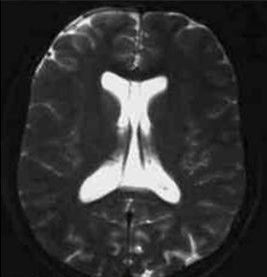

第六腦室(Verga氏腔)又稱穹隆狀腔,大多由海馬連合閉合不全所致,不屬於腦室系統,常由第五腦室向後擴展形成,亦可單獨存在。

基本信息 植物形態 藥代動力學 藥理作用 商品化學成分簡介蛛網膜下隙在腦的溝、裂等處擴大,形成蛛網膜下池,亦稱腦池。此概念可與腦室概念一起理解,腦室即腦內部的腔隙,腦室系統包括側腦室、第三腦室和第四腦室(有時還可見第五或第六腦室),各腦室之間有小孔和管道相通。 成對腦...